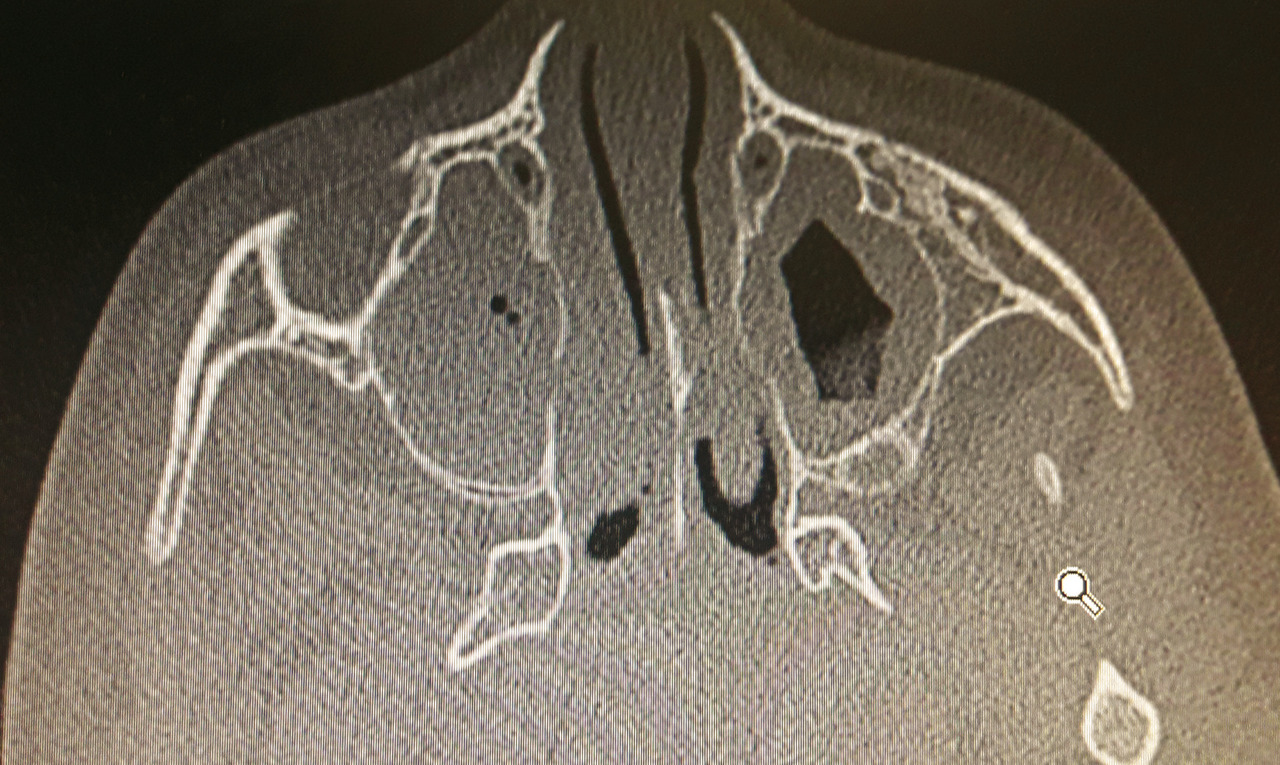

Une tomodensitométrie avec injection de produit de contraste est indiquée d’emblée si l’œil n’est pas ouvrable spontanément, s’il y a une limitation des mouvements de l’œil ou une exophtalmie, mais aussi chez l’enfant de plus de 9 ans ou en cas d’absence d’amélioration clinique après 24 heures de traitement.4 Elle confirme l’ethmoïdite et surtout recherche une complication intracrânienne, particulièrement un abcès sous-périosté intra-orbitaire (fig. 3 ).

Une tomodensitométrie avec injection de produit de contraste est indiquée d’emblée si l’œil n’est pas ouvrable spontanément, s’il y a une limitation des mouvements de l’œil ou une exophtalmie, mais aussi chez l’enfant de plus de 9 ans ou en cas d’absence d’amélioration clinique après 24 heures de traitement.4 Elle confirme l’ethmoïdite et surtout recherche une complication intracrânienne, particulièrement un abcès sous-périosté intra-orbitaire (